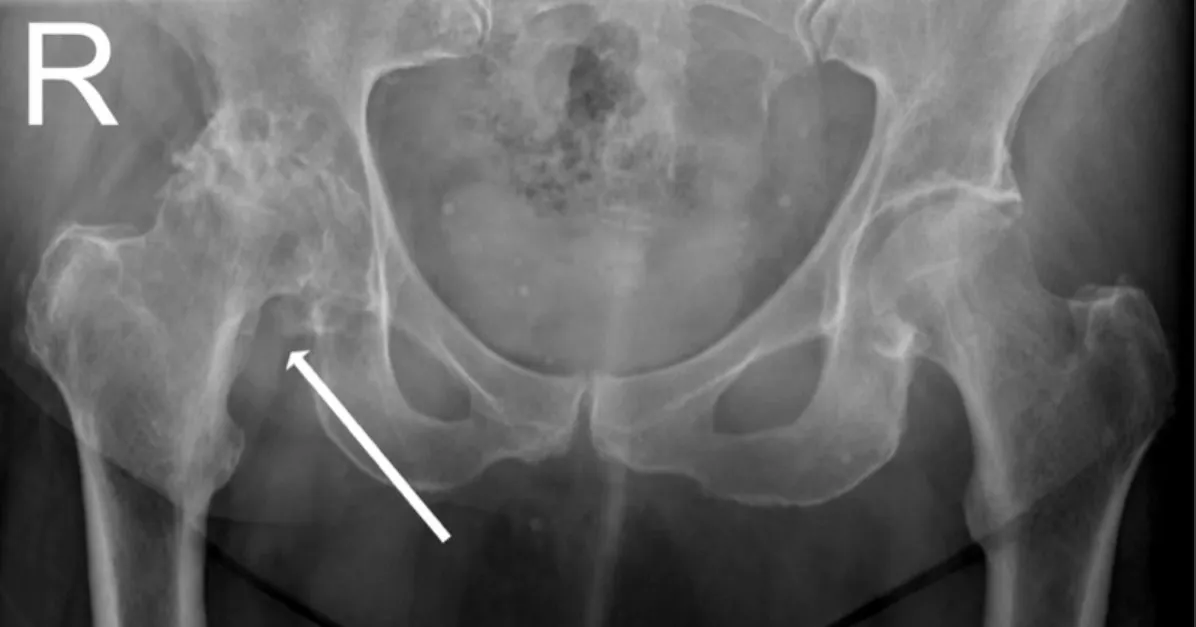

透過 X 光檢查,我們可以清楚看到關節退化的程度。正常的髖關節,圓球狀的股骨頭與骨盆之間應該有一條黑色的縫隙,那就是健康的軟骨。

但在退化性關節炎的影像中(如下圖),您會發現:

- 關節間隙變窄: 如下圖箭頭所示,原本的縫隙消失了,代表軟骨已經磨損殆盡,變成「骨頭磨骨頭」。

- 骨刺增生 (Osteophytes): 骨頭邊緣長出尖銳的骨刺。

- 軟骨下骨硬化 (Sclerosis): 骨頭顏色變白、變硬。